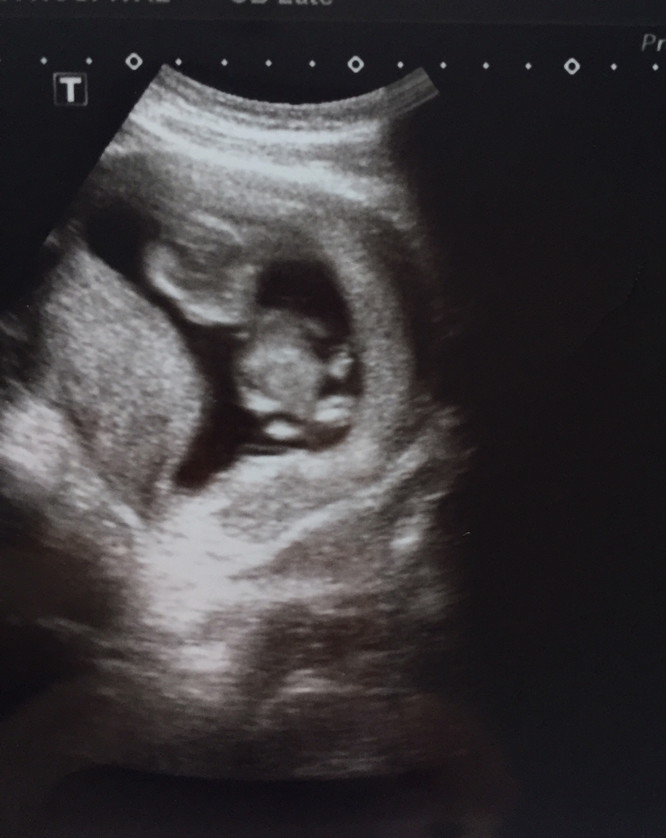

แม่ๆคนไหนมีภาพอัลตร้าซาวด์ประมาณ13วีคบ้างคะ ของเรา13วีค ภาพแบบนี้ค่ะ ดูไม่ออกเลย?

ช่วง 13 วีคค่ะ